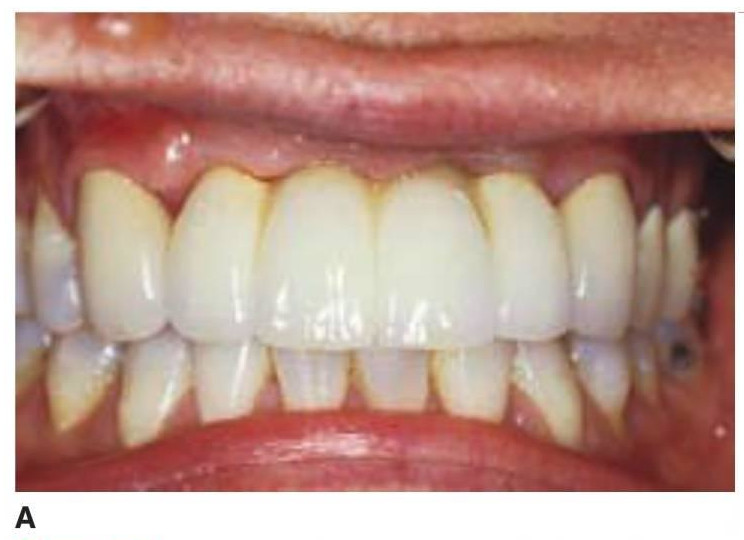

Básicamente existen dos enfoques para una prótesis PF-3: 1) una restauración híbrida compuesta por una dentadura con dientes con una subestructura acrílica y metálica o 2) una restauración de metal-porcelana (figs. 5-12 a 5-14; tabla 5-2).

Una alternativa a la prótesis tradicional fija de metal porcelana es la restauración híbrida (v. tabla 5-2). Este di seño utiliza una estructura metálica menor, con dientes artificiales y acrílico para unir estos elementos (fig. 5-15).

Esta restauración es menos cara de fabricar y es muy estética debido a los dientes artificiales prefabricados y al reemplazo de los tejidos blandos por el acrílico rosa. Además, el acrílico interpuesto entre los dientes y el armazón puede reducir fuerza de impacto de las cargas odusales dinámicas. La prótesis híbrida es más fácil de reparar ante una fractura, y el diente artificial puede sustituirse con un riesgo menor que el añadido de porcelana a una restauración tradicional ceramometálica. En cualquier caso, la fatiga del acrílico es mayor que en las prótesis tradicionales; de ahí que la reparación de la restauración se necesite con más frecuencia.